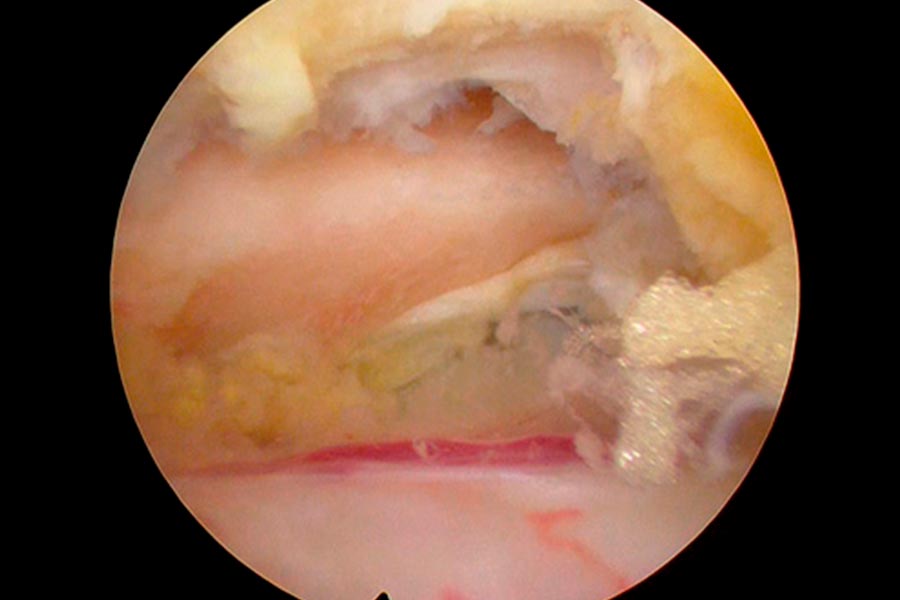

Caso clínico: endoscopia de columna multinivel L4L5 y L5S1

Durante la intervención quirúrgica, se abordarán los dos niveles mediante la técnica de endoscopia de columna.